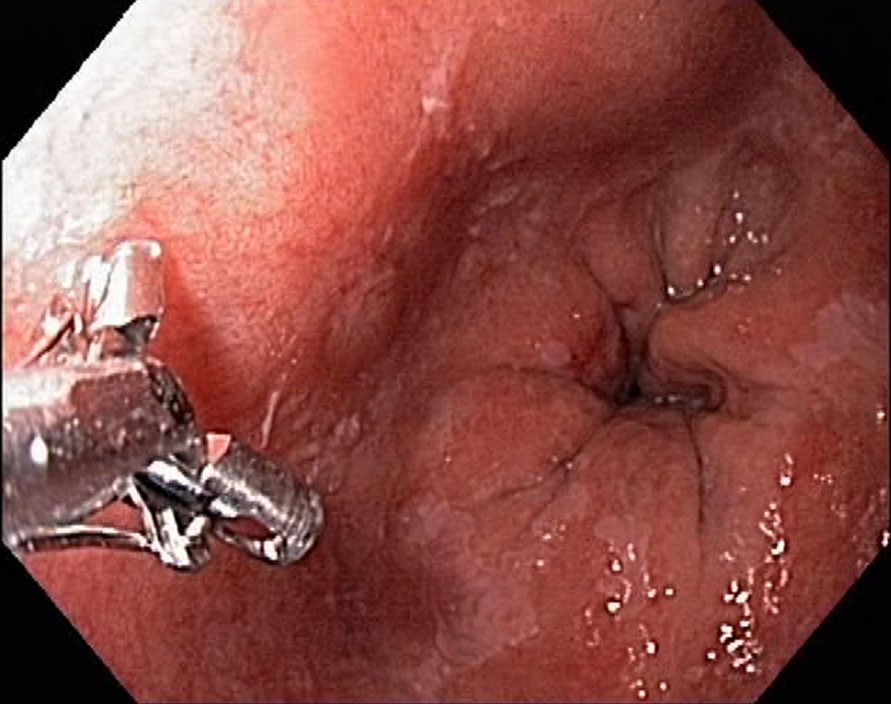

Barrets Oesophagus (NBI, Narrow Band Imaging)